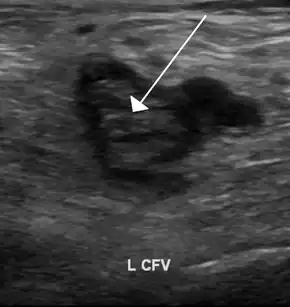

An ultrasound image demonstrating a blood clot in the left common femoral vein. | |

The most common conditions associated with thrombophilia are deep vein thrombosis (DVT) and pulmonary embolism (PE), which are referred to collectively as venous thromboembolism (VTE). DVT usually occurs in the legs, and is characterized by pain, swelling and redness of the limb. It may lead to long-term swelling and heaviness due to damage to valves in the veins.[6] The clot may also break off and migrate (embolize) to arteries in the lungs. Depending on the size and the location of the clot, this may lead to sudden-onset shortness of breath, chest pain, palpitations and may be complicated by collapse, shock and cardiac arrest.[2][7]